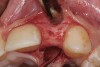

A 9-year-old girl, referred to a prosthodontic office by her pediatric dentist, presented with her mother’s chief complaint: “The kids are teasing her about her big front tooth.” Findings from radiographic and clinical examinations revealed fused maxillary central-peg lateral incisors, teeth Nos. 7 and 8, and a congenitally missing lateral incisor, tooth No. 10 (Figure 1 through Figure 3). An implant was selected as the ideal treatment to replace tooth No. 10 when somatic growth was complete. A diagnostic wax-up was fabricated to determine if the fused tooth could be made to resemble two teeth, using pink composite to give the illusion of an interproximal papilla. The patient was referred for an orthodontic consultation to plan for closure of the diastema between teeth Nos. 8 and 9 and achievement of proper alignment for implant No. 10. The patient was also referred to a periodontist for pretreatment assessment of the tooth No. 10 site. An endodontist was consulted should exposure of the large pulp occur during tooth preparation.

Fig 1 and Fig 2. Pretreatment photographs. Patient at 9 years of age on presentation.